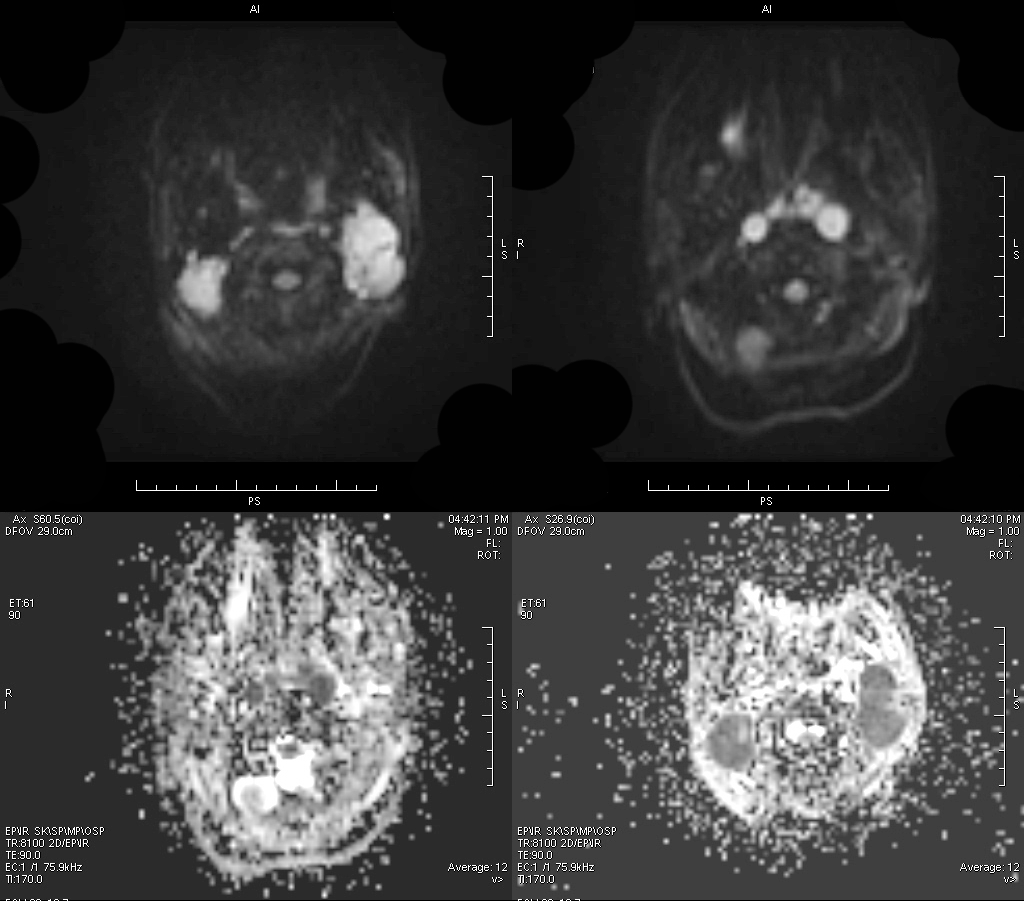

MRI 表现:鼻咽后壁及两侧壁不规则软组织肿块,信号多较均匀,T1WI 像呈等信号,T2WI 像呈稍高信号,DWI 像为明显高信号。增强扫描肿块常轻-中度均匀强化,液化坏死少见。颈部淋巴结肿大常见。肿大淋巴结多边缘规则,内部密度或信号均匀,增强扫描轻度强化。对邻近组织侵犯少,肿块与咽后壁头长肌等分界清楚,多无颅底及相邻骨质破坏。鼻咽部肿块虽较明显,但咽旁间隙较清晰,或只有受压改变。

MRI 表现:早期表现为鼻咽顶后壁轻度软组织增厚、突起,表面不规则、边界不清;咽隐窝变浅甚至消失,鼻咽轮廓改变,双侧结构不对称;进展期肿瘤增大向周围组织、结构浸润生长,并可破坏颅底骨质结构,以中线部蝶骨体和枕骨斜坡最常见。肿瘤在 T1WI 像上呈中等或中低信号,T2WI 像上呈中等或中高信号,边缘模糊呈浸润状;增强扫描多呈明显强化,肿块内坏死区无强化。颈部较小的转移淋巴结边缘多较清楚、信号均匀;较大的淋巴结中央常见液化坏死,多发增大的淋巴结可融合呈巨大的肿块,信号不均匀。